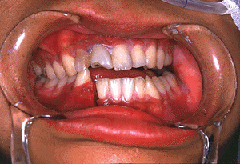

下顎骨骨折の例をお見せしましょう。

顎の骨が折れました!

右下顎側切歯と犬歯の間がずれてしまっていますね!!

こうなると、噛むたびに割れた骨がずれて痛くてご飯も食べれません!!!